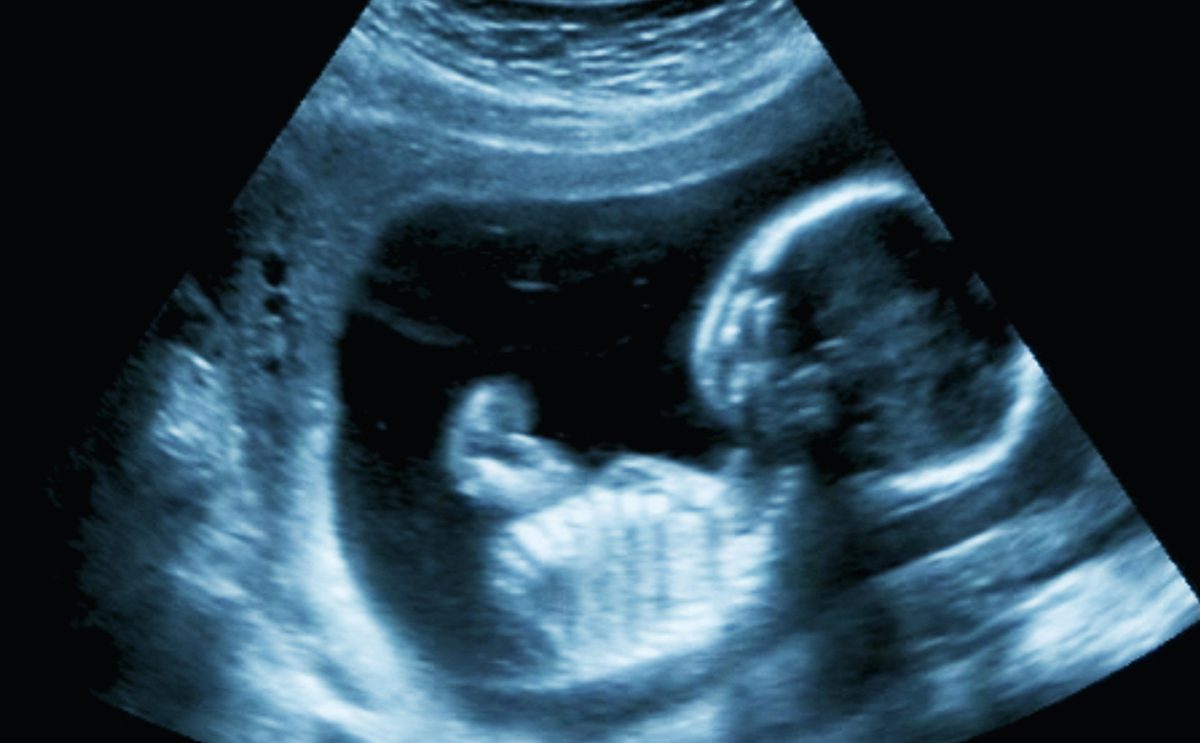

هو جهاز يتم وضعه على الرحم من أجل التمكن من تحديد شكل الجنين وكيفية تحركة والوضعية التي يتخذها. يتمكن الطبيب من التفرقة بين أعضاء الجنين إذ تكوني الأنسجة الصلبة ملونة باللون الأبيض والأنسجة الناعمة باللون الرمادي. أما السائل الأمنيوسي فيكون لونه أسود.

خلال المرحلة الأولى من الحمل، يقوم الطبيب بفحص ضربات قلب الجنين والتأكد من أنها تنبض بشكلٍ طبيعي ومن ثم يقوم بالتدقيق على رأس الطفل وجدار بطنه.